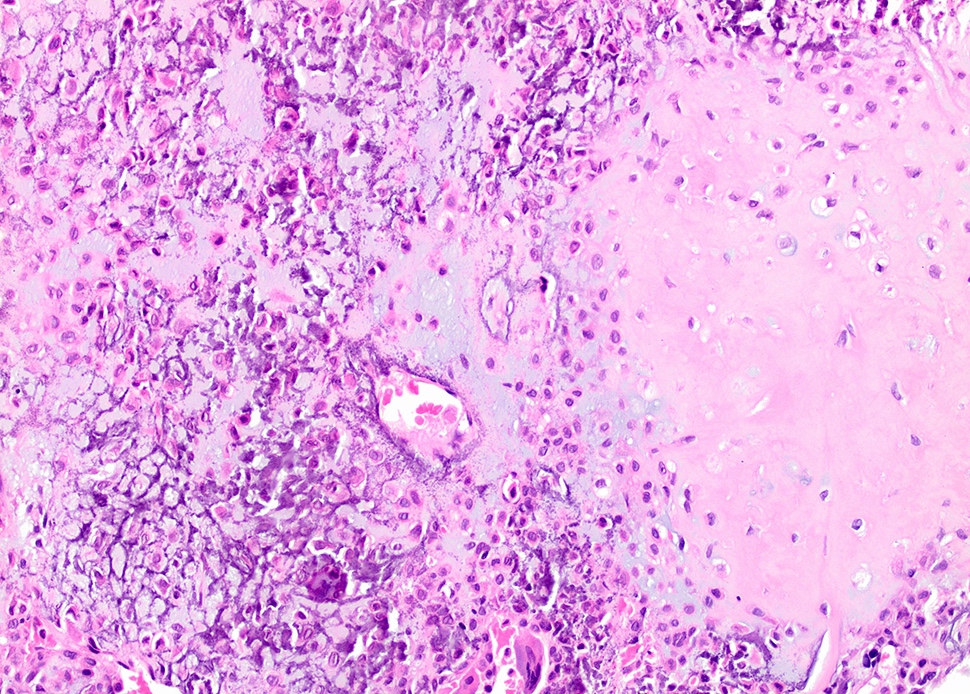

Microscopic (histologic) images

- Composed of round or polyhedral chondroblasts with abundant eosinophilic cytoplasm and well defined cell borders; spindle shaped cells may be focal (Ann Diagn Pathol 2003;7:205, Cancer 1972;30:401)

- Nuclei are oval, hyperlobulated with grooves

- Pericellular lace-like or chicken wire type calcification among degenerative chondroblasts

- Chondroid matrix almost always present (pink rather than blue matrix)

- May have marked cellularity, intracytoplasmic glycogen granules, mitotic figures, necrosis and osteoclast type giant cells

- No significant nuclear atypia as compared with malignant chondroblastoma (Mod Pathol 2020;33:2295)

- Aneurysmal bone cyst-like change is common (Skeletal Radiol 2010;39:583)